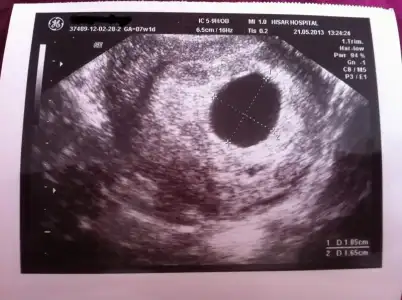

valla canım bende hep vajinal oluyorum muayene zaten..ama görünmüyo işte..bak 2 gün önceki ultrason görüntüm bu :50:

$ultrason.webp